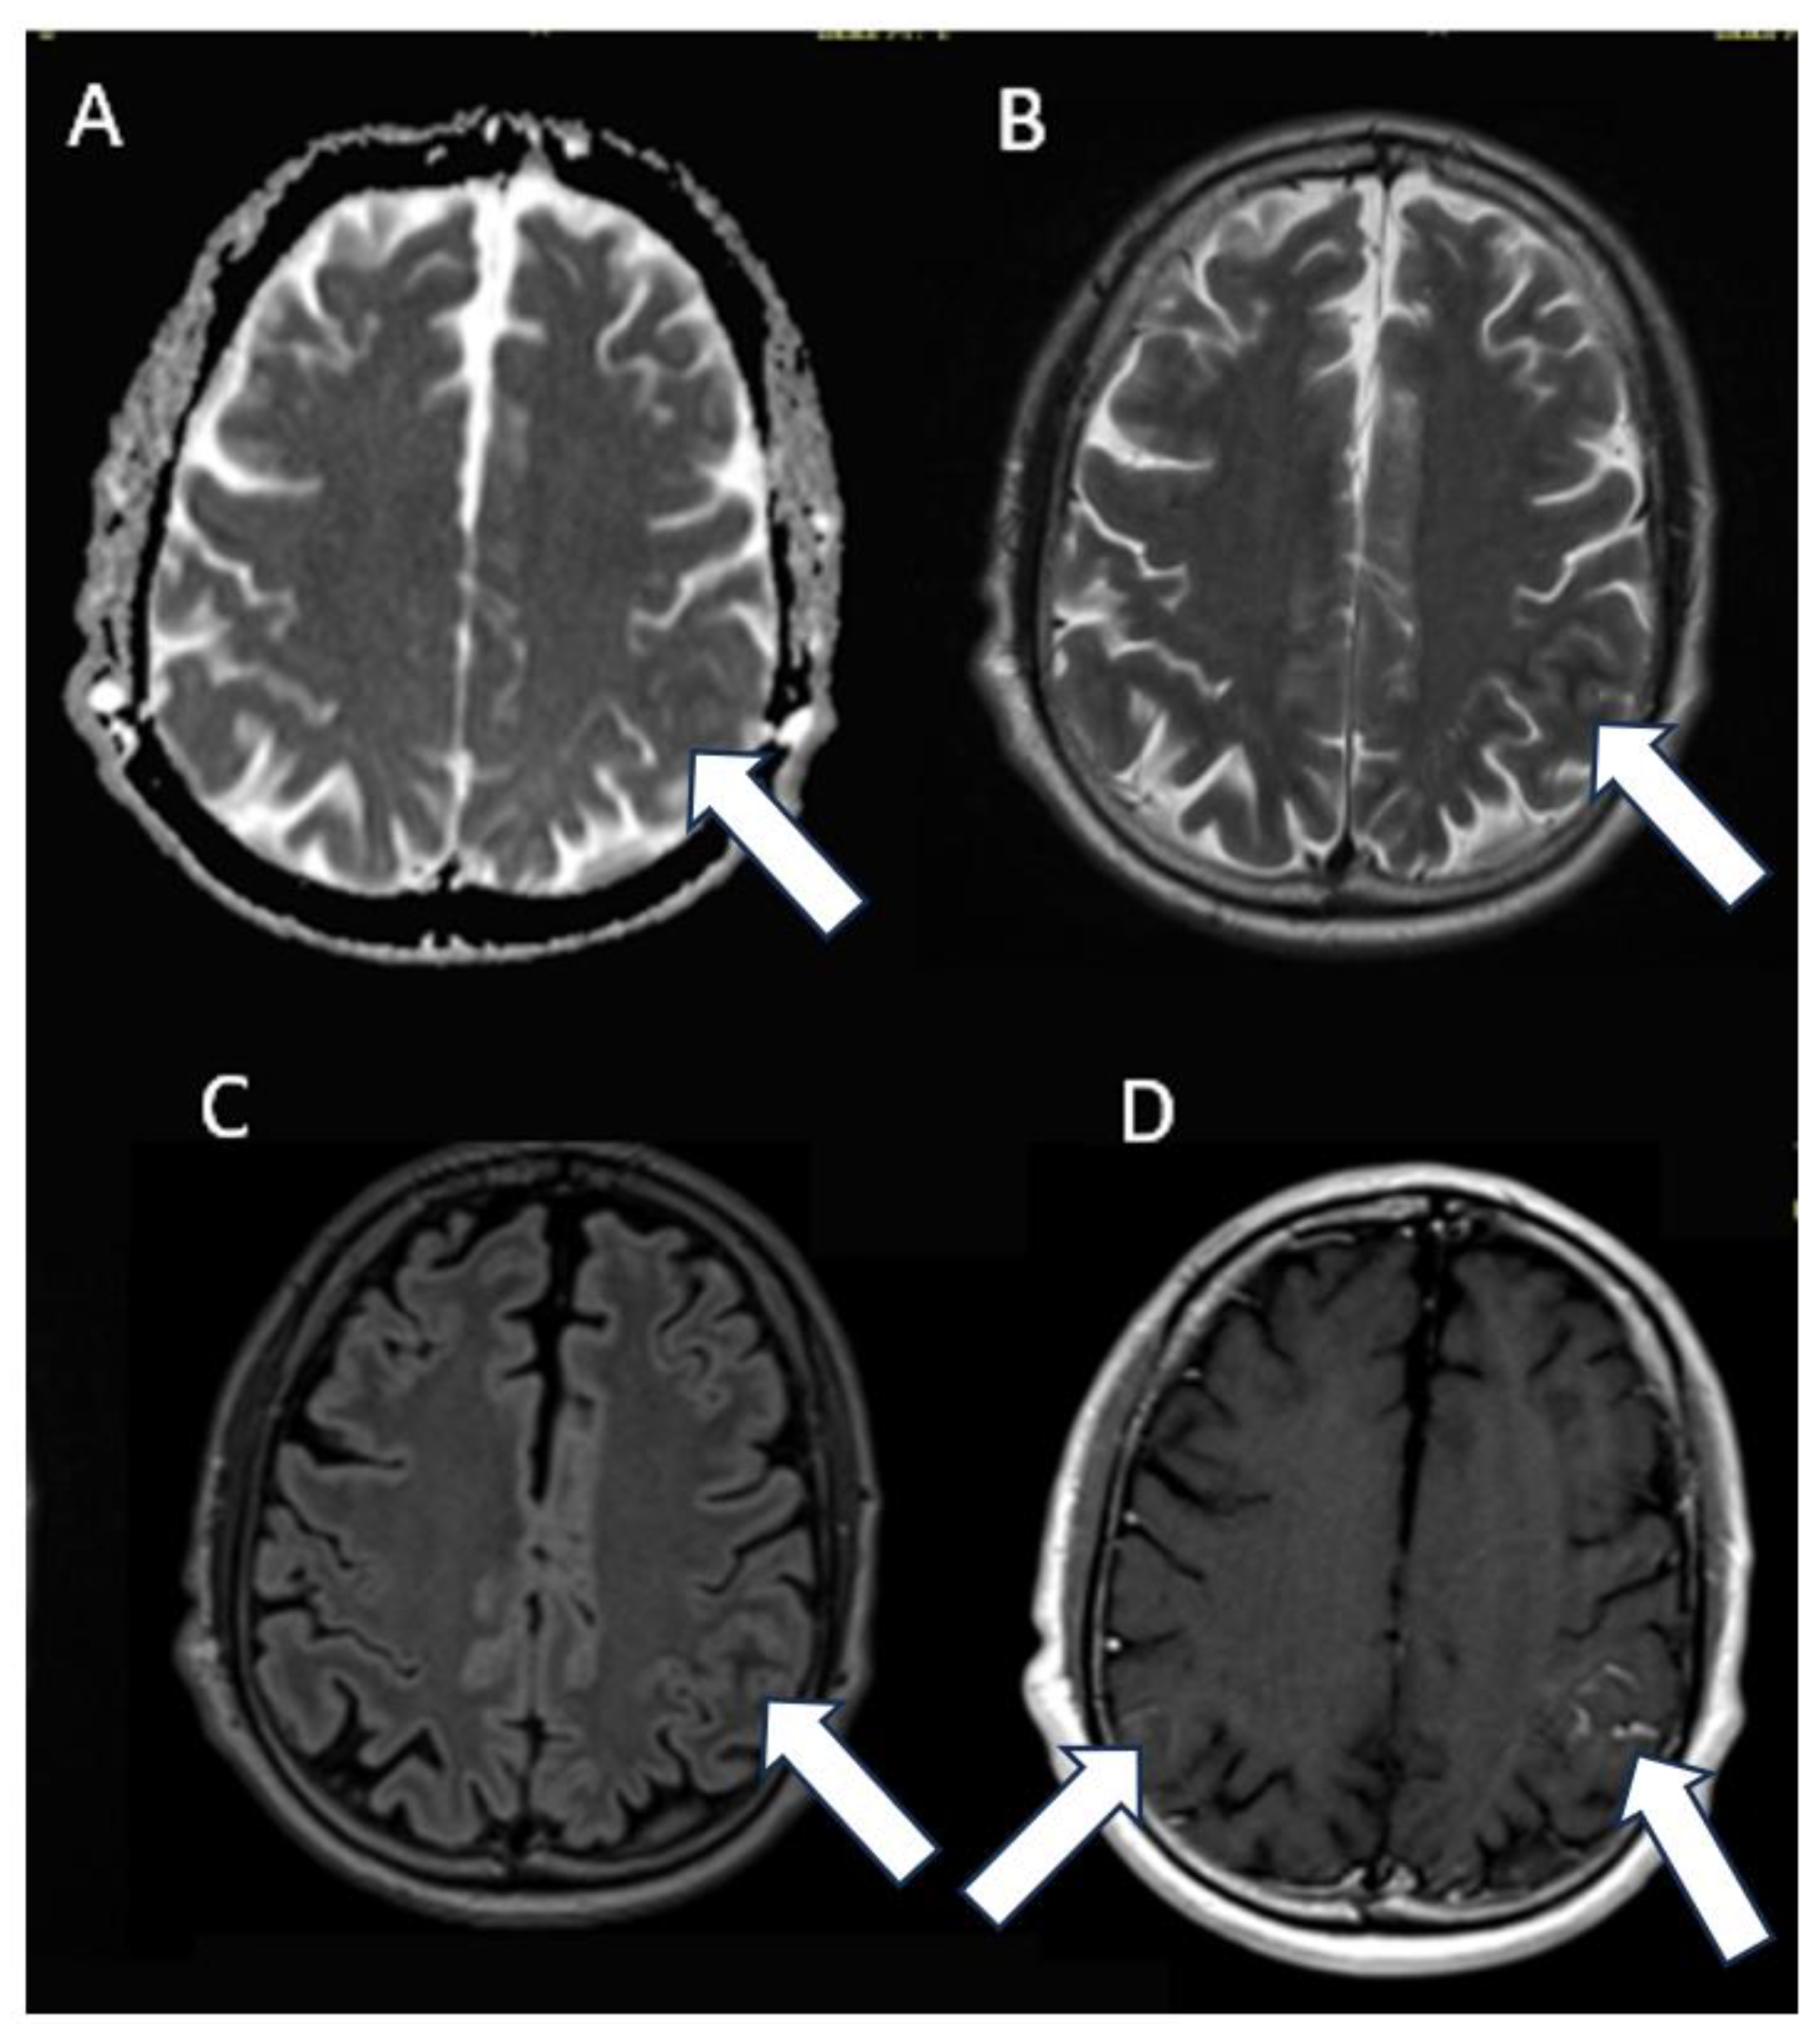

Figure 2.

MRI axial images: (A) apparent diffusion coefficient (ADC) map, (B) T2-weightd image, (C) fluid-attenuated inversion recovery (FLAIR) image, and (D) post-contrast T1-weighted image. MRI imaging confirmed the abnormal signal (arrows) of subarachnoid spaces in left parietal region associated not to diffusion restriction but to leptomeningeal contrast enhancement. Similar less evident findings are also on the right side (arrow).